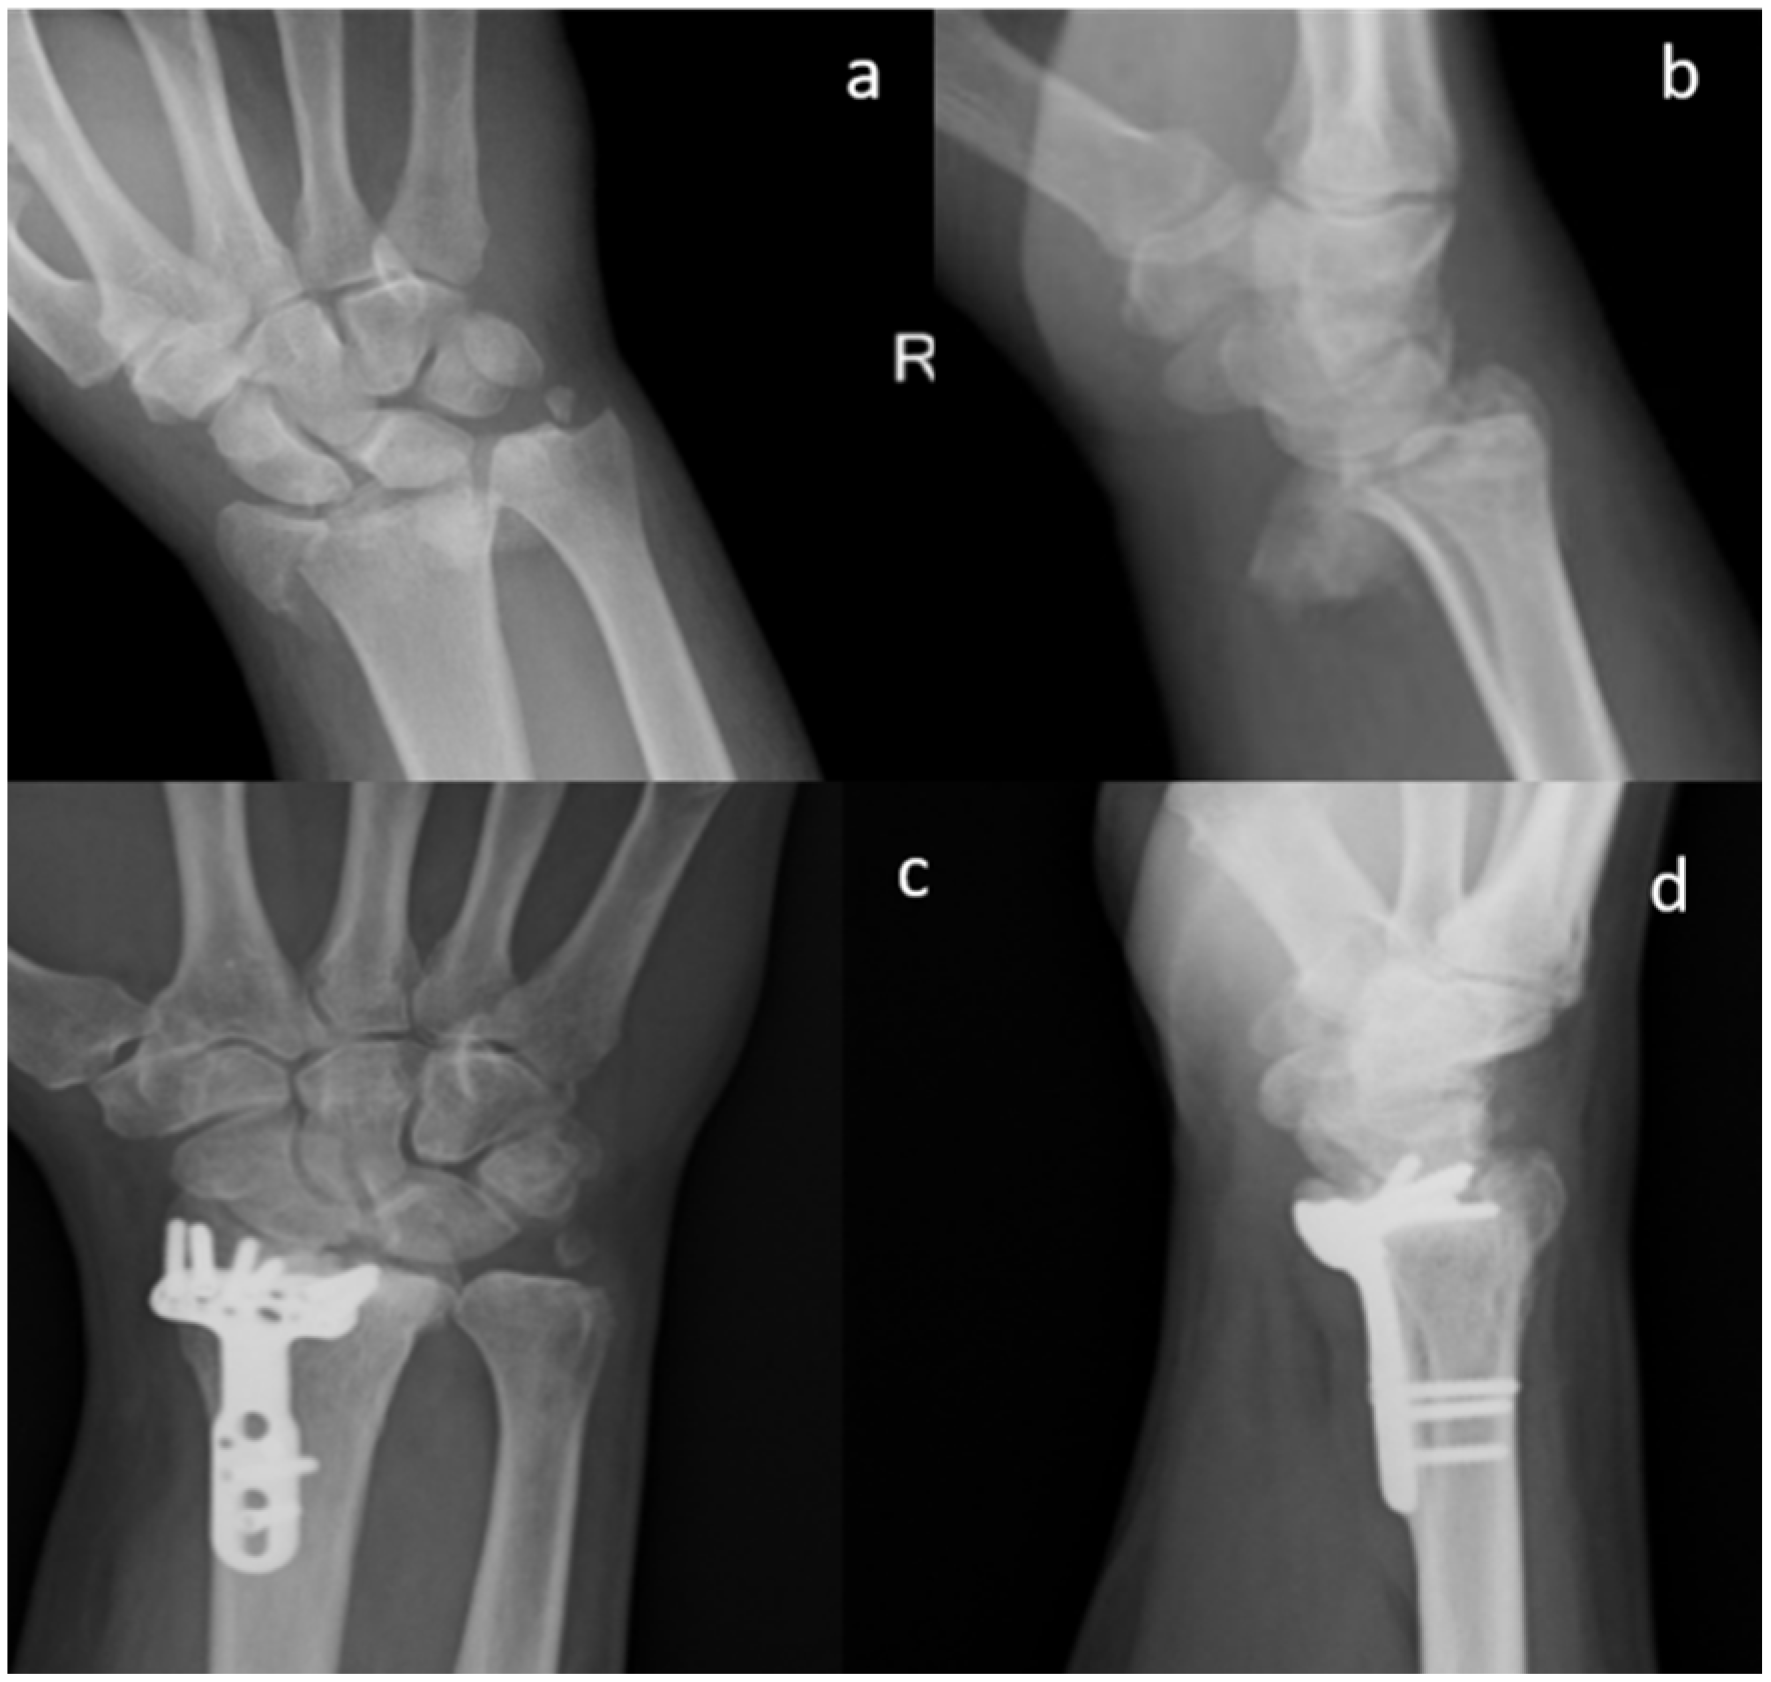

All the patients performed radiographic examinations during regular follow-up. Radiographs were examined for callus formation, bone resorption, implant stability, and SB integration [28] (Figure 1, Figure 2 and Figure 3).

X-ray images of 7 out of 19 patients showed that fractures were consolidated at two months: the radiographic controls, indeed, showed abundant callus formation. An exemplificative case is presented in Figure 2. The remaining 12 patients showed reduced callus formation after two months and performed an additional X-ray imaging check at five months after surgery (exemplificative case shown in Figure 3). In all cases, radiolucency of the xenografts was assessed, which became progressively more similar to that of the surrounding healthy bone tissue.